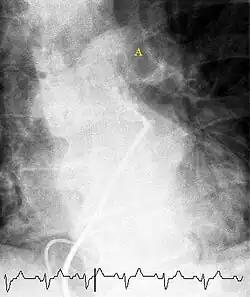

Fluoroscopic pulmonary angiography

Historically, the gold standard for diagnosis was pulmonary angiography by fluoroscopy, but this has fallen into disuse with the increased availability of non-invasive techniques that offer similar diagnostic accuracy.[71]

Pulmonary angiography has for decades remained the 'gold standard' for the diagnosis or exclusion of PE but is rarely performed now as less-invasive CT angiography offers similar diagnostic accuracy.